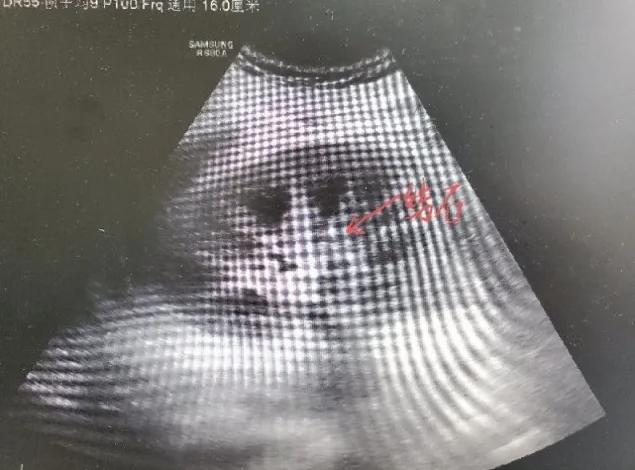

小柯接受了血液透析治疗,帮助肾脏清除体内毒素。进一步肾穿刺活检发现,小柯多处肾小管内存在钙化样物,超声显示双肾存在多发结石!